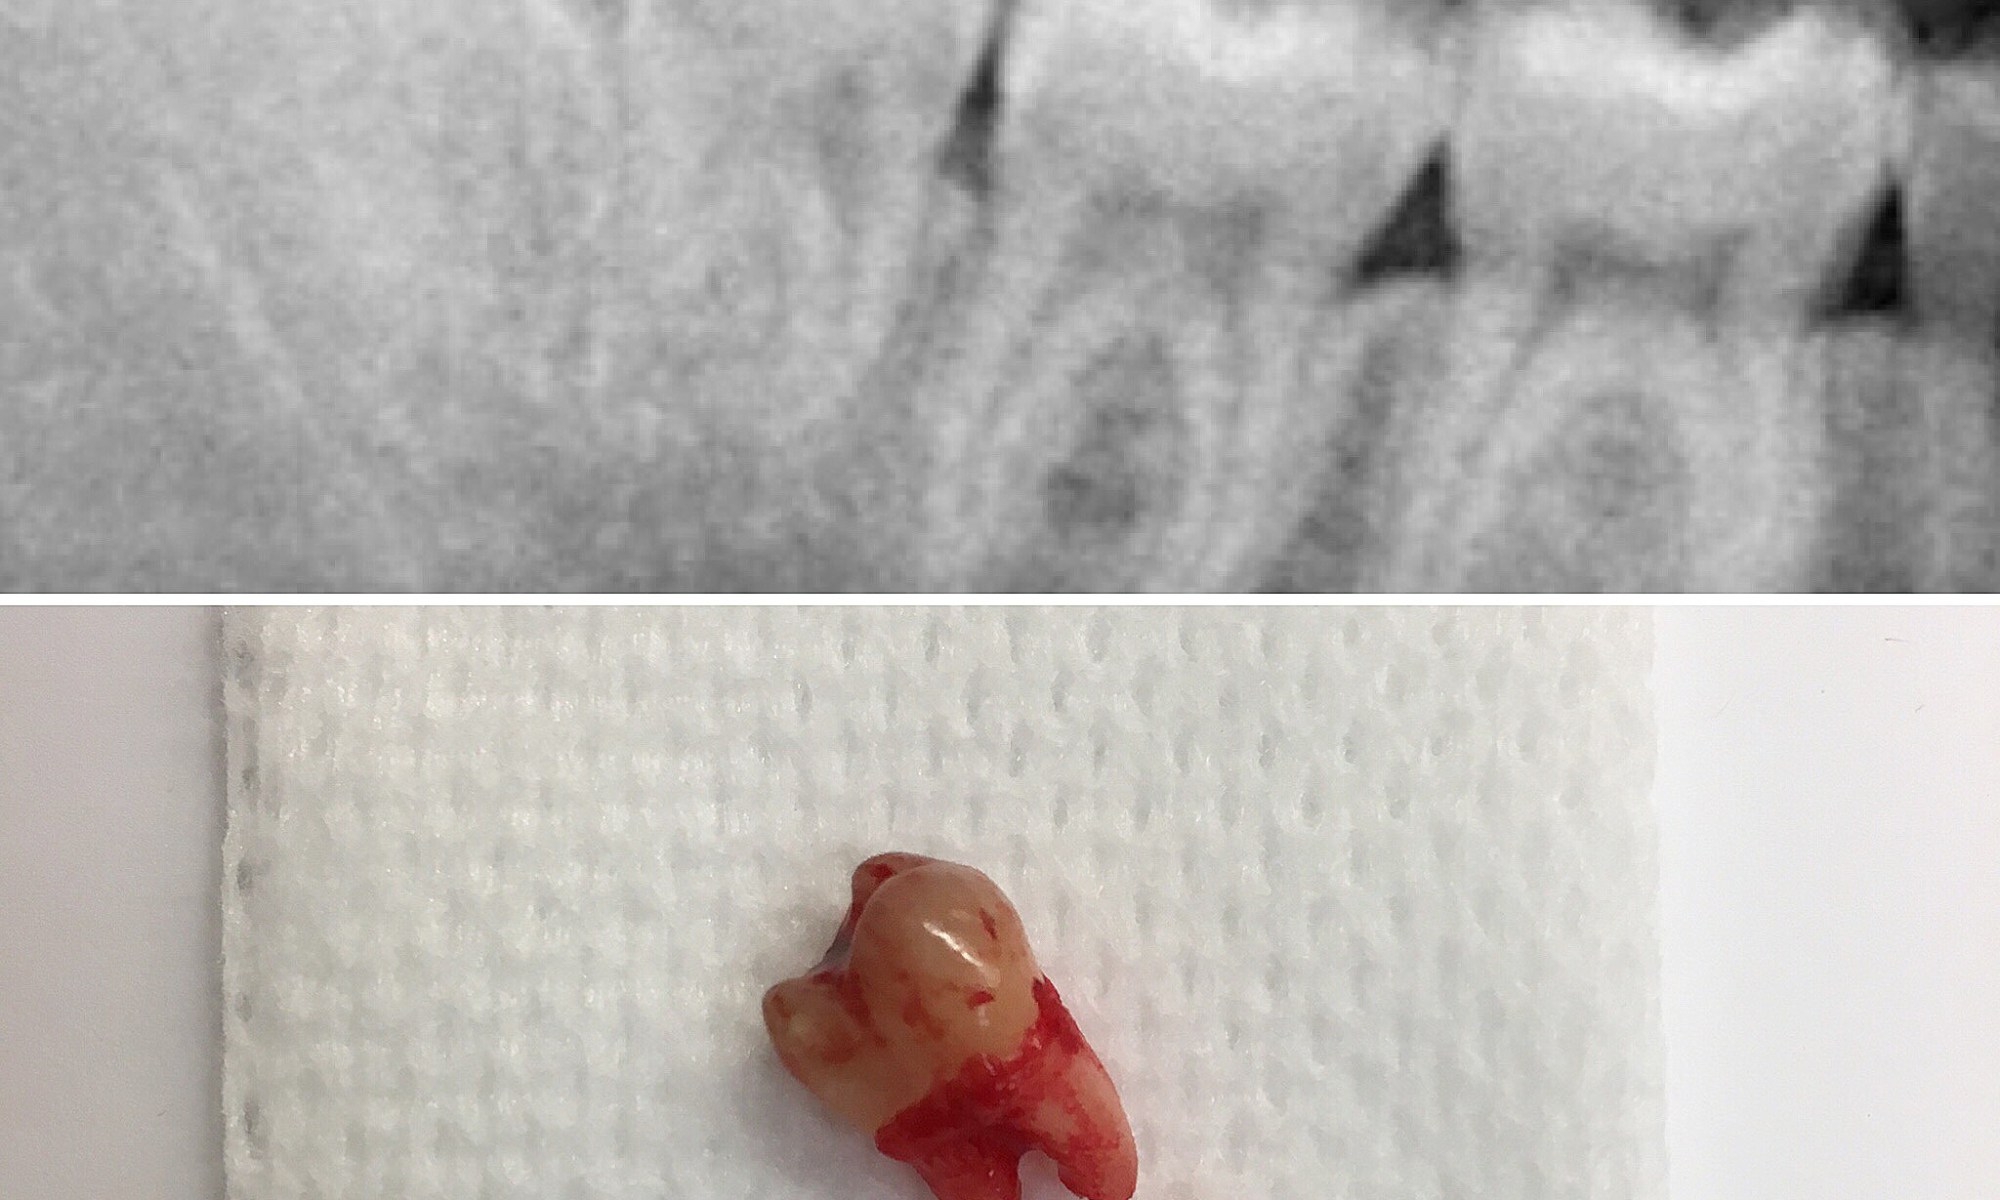

Had a fun time treating our hygienist’s brother under laughing gas. Look at the root of this wisdom tooth – 90 degree curve! Glad we got it out!